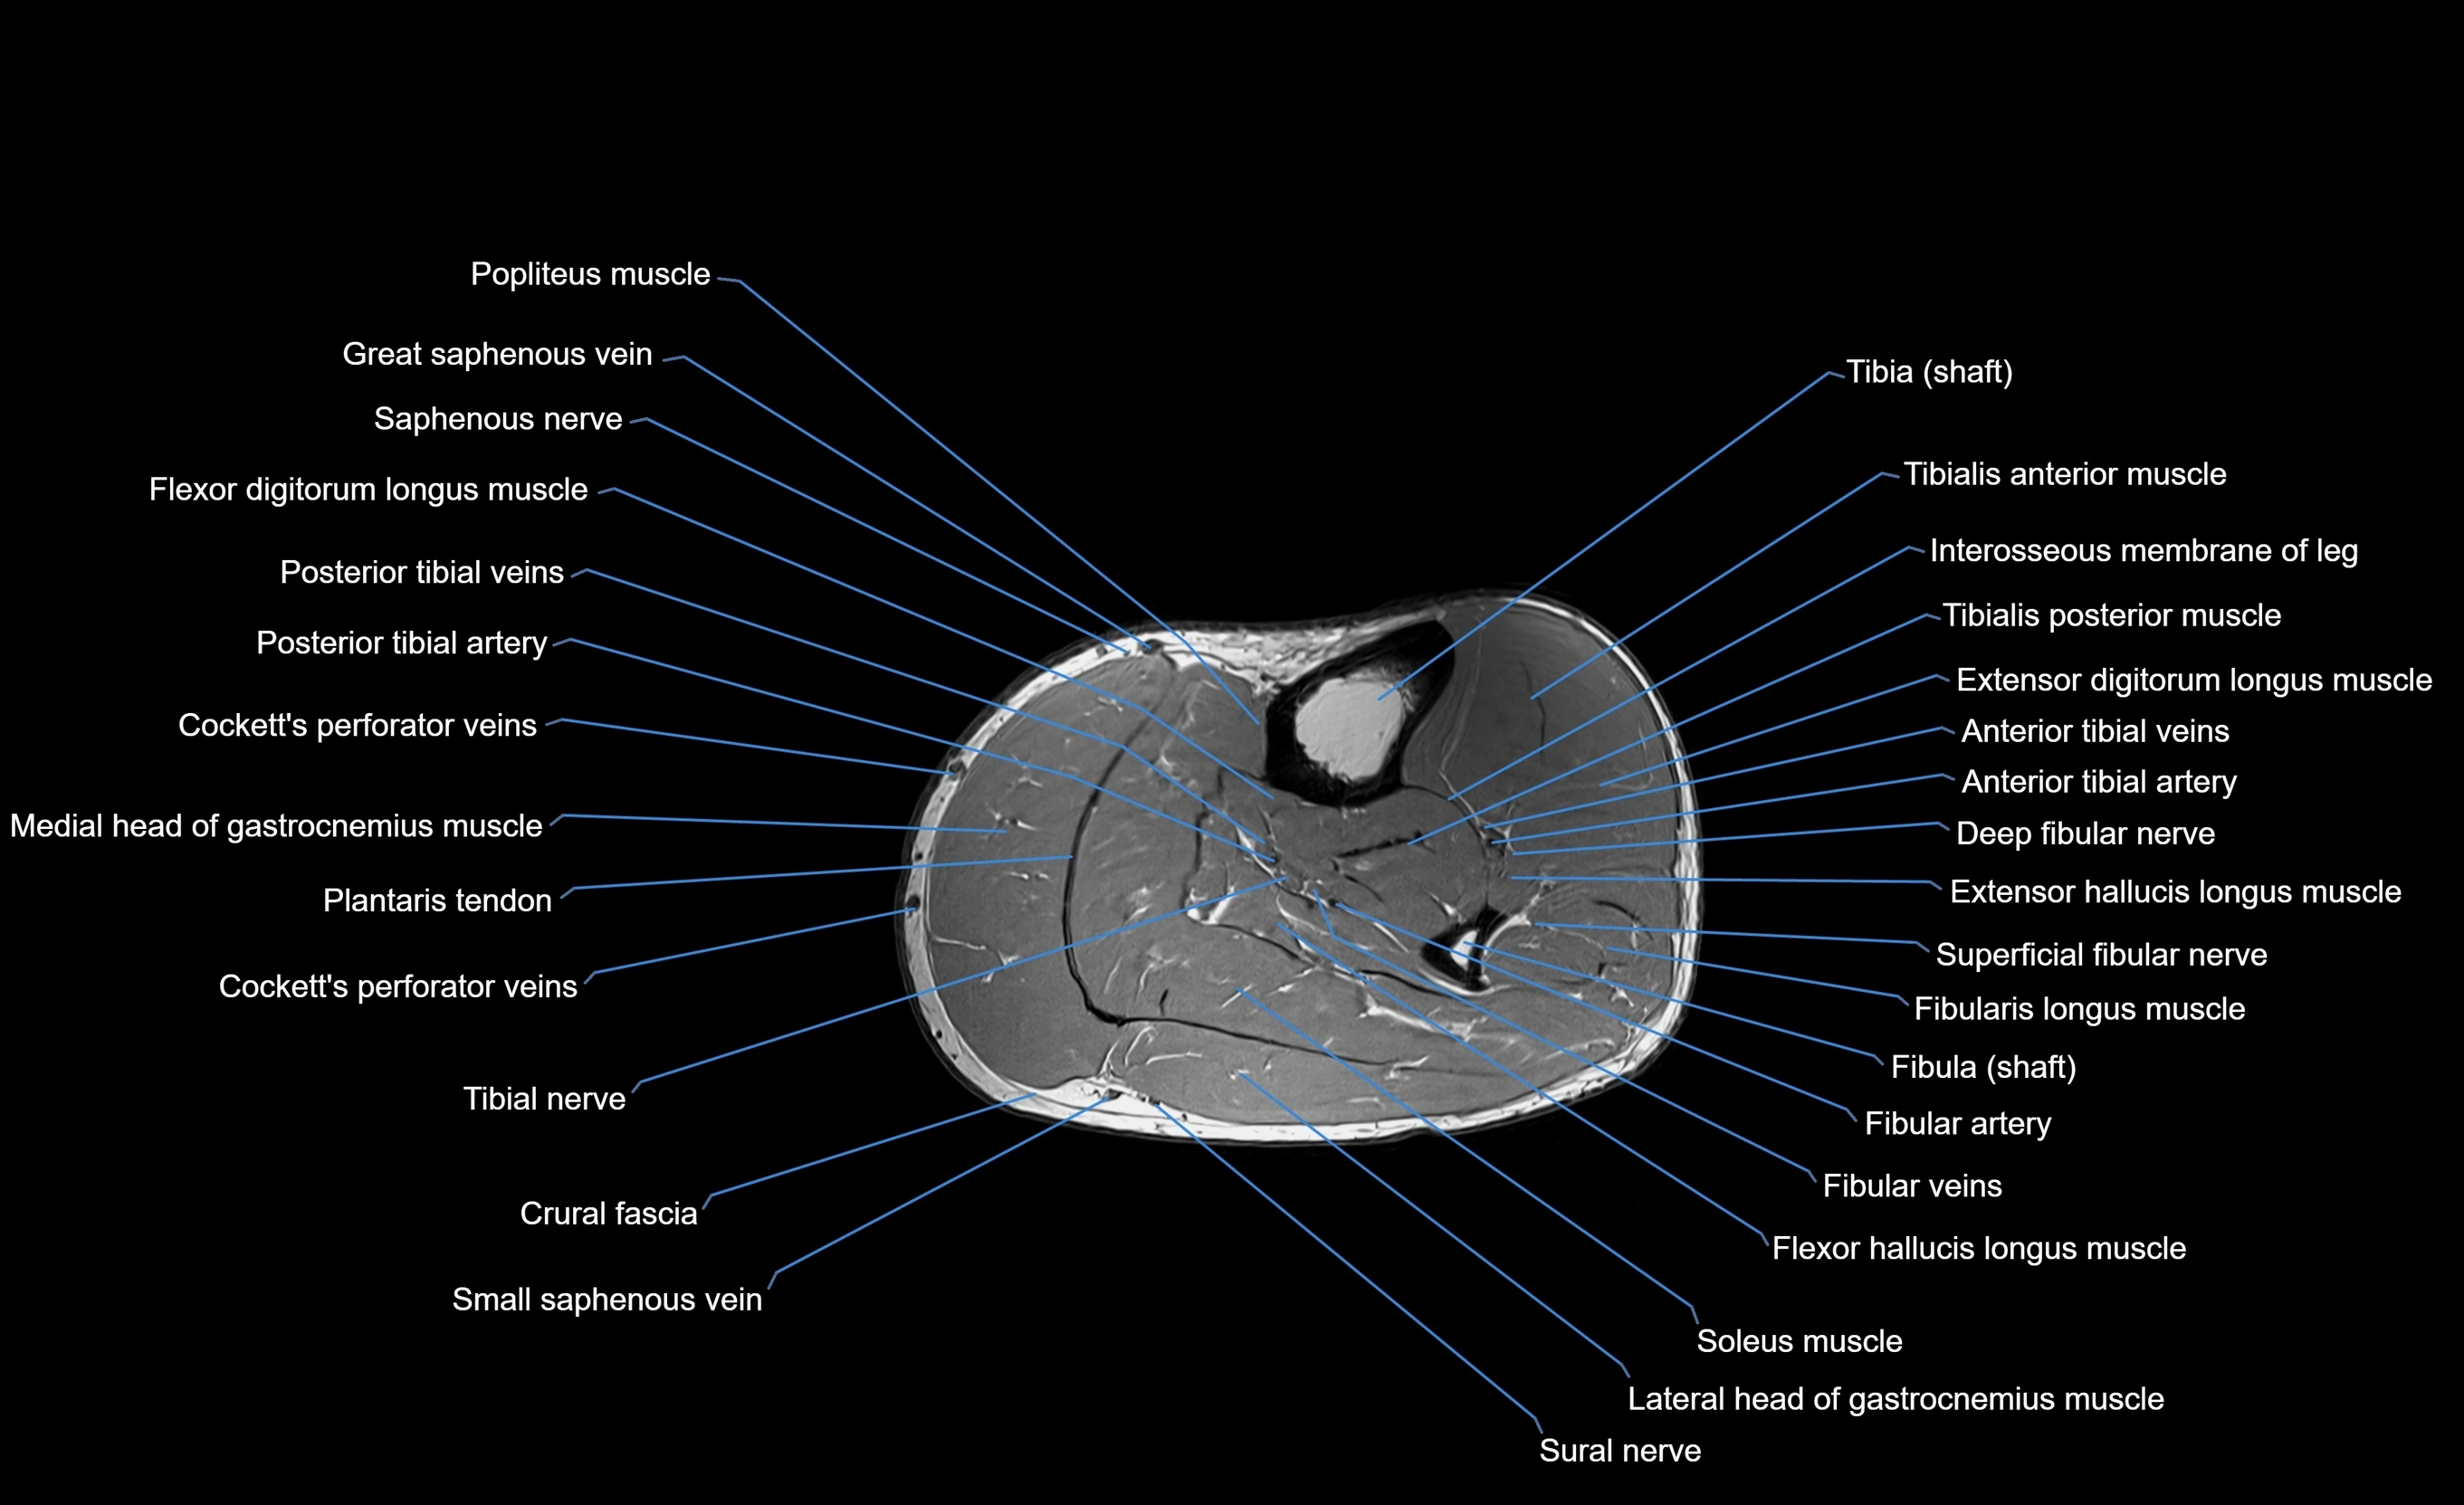

MRI image